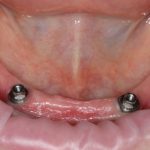

Рекомендации по установке имплантов. Для всех. Часть III